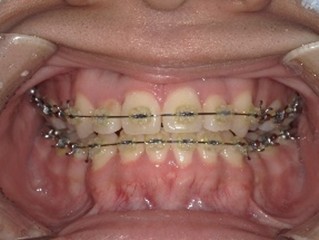

(初診時) (ワイヤー矯正後) (マウスピース矯正後)